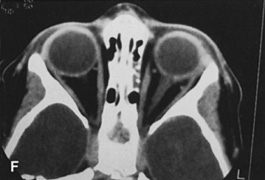

Figure 10. A. Large, well-encapsulated intraconal mass on MR scan. B. Small lateral canthotomy incision will be used to perform lateral orbitotomy and remove the intraconal mass.

Fig. 11. A. Lateral canthotomy incision is made with straight iris scissors. B. Periosteum is elevated off of the lateral orbital rim. C. Wide undermining allows retraction of the skin incision to permit superior and inferior osteotomies to be made with the air-driven saw. D. The bony rim has been outfractured. Because of the distensibility of the skin, it is possible to remove a large bone flap through the small canthotomy incision. E. The intraconal mass is extracted with the aid of the cryoprobe. F. The bone fragment is positioned for resuturing.

Fig. 12. A. The lateral canthotomy incision is reapproximated with simple closure of the superior and inferior crura of the lateral canthal tendon. A drain from the temporal fossa has been brought out through a separate stab incision posteriorly. 12B. Excellent postoperative scar camouflage is obtained by this approach.